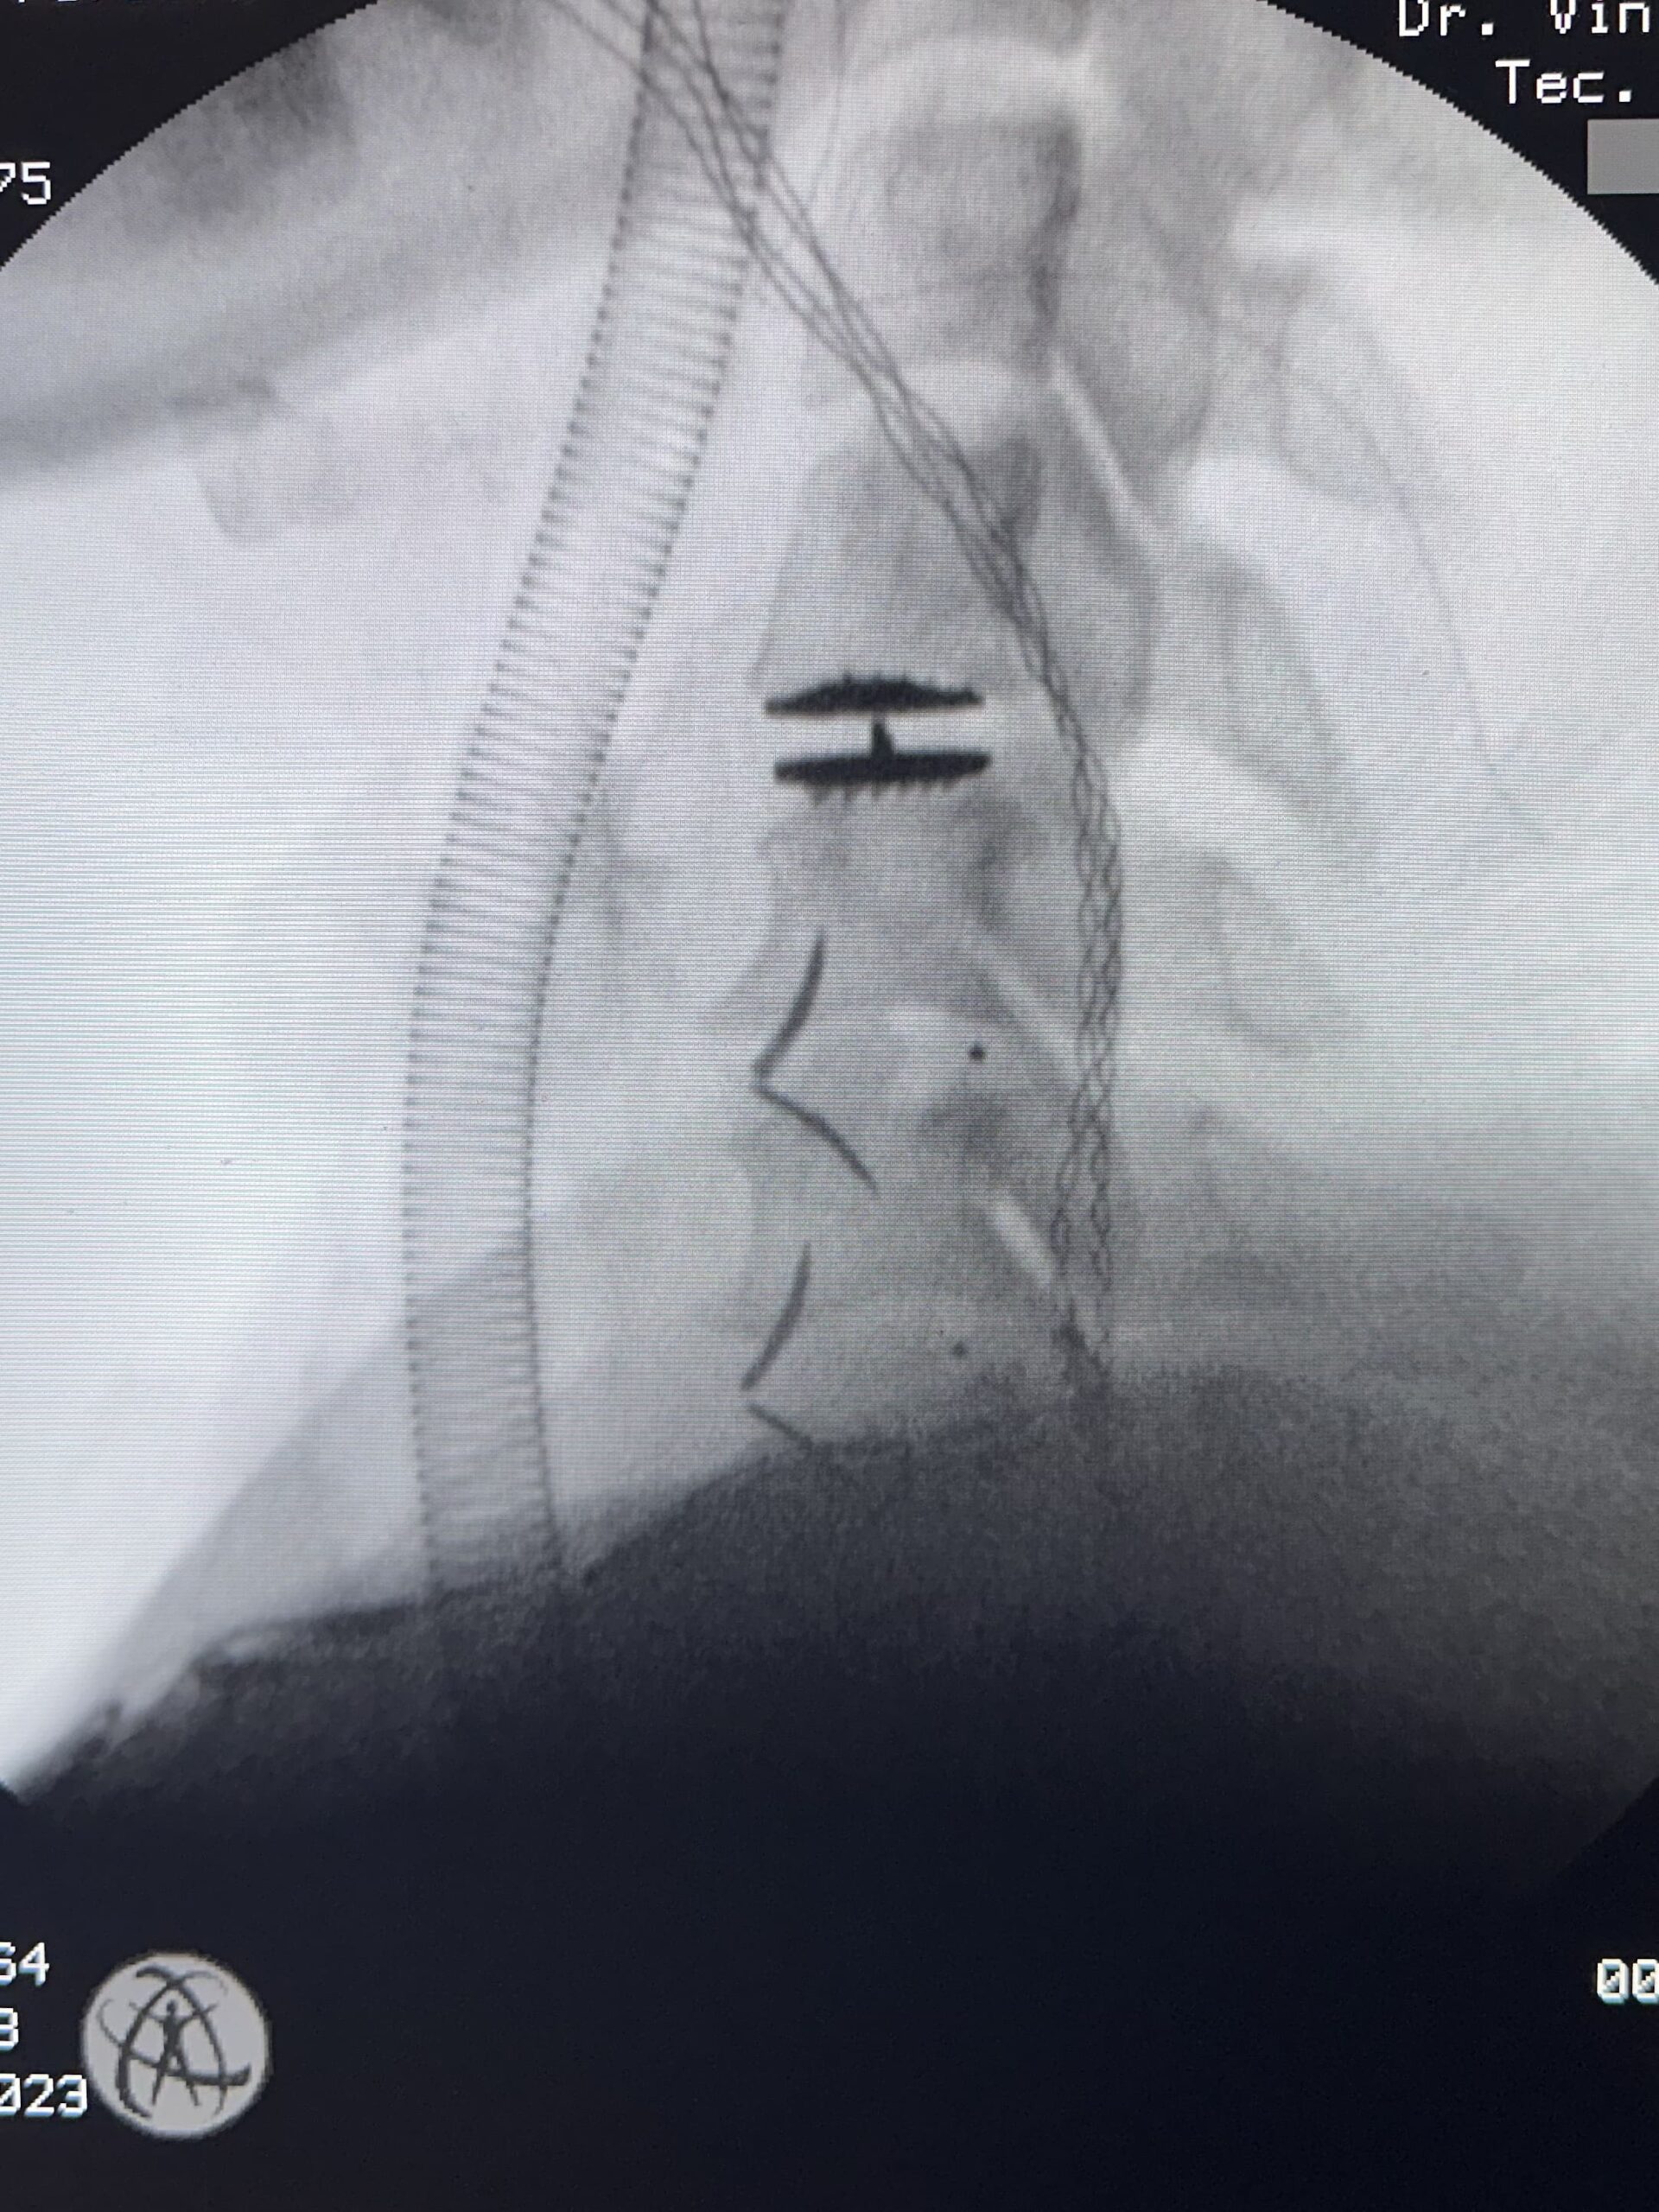

As duas principais técnicas cirúrgicas para hérnia de disco cervical são:

A artrodese cervical é um procedimento cirúrgico que envolve a fusão de duas ou mais vértebras da coluna cervical. A fusão é realizada usando parafusos, pinos ou placas.

A artrodese cervical é indicada para casos de hérnia de disco cervical que não responderam ao tratamento conservador ou que causam dor significativa.